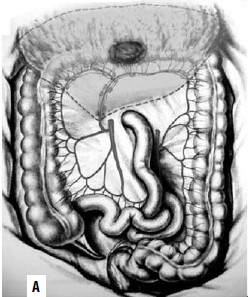

По топографии лимфометастазов рака слепой и восходящей ободочной кишки для радикального удаления зон регионарного метастазирования необходима правосторонняя гемиколэктомия с резекцией 25–30 см тонкой кишки, перевязкой и пересечением основных стволов a. Ileocolica и a. colica dextra (рис. 187). Одним блоком с кишкой удаляется забрюшинная клетчатка с лимфатическими узлами. При раке печеночного изгиба и проксимальной трети поперечной ободочной кишки удалению подлежит лимфоколлектор по ходу a. colica media (рис. 188). Операция заканчивается формированием илеотрансверзоанастомоза (анастомоза между подвздошной и поперечной ободочной кишкой).